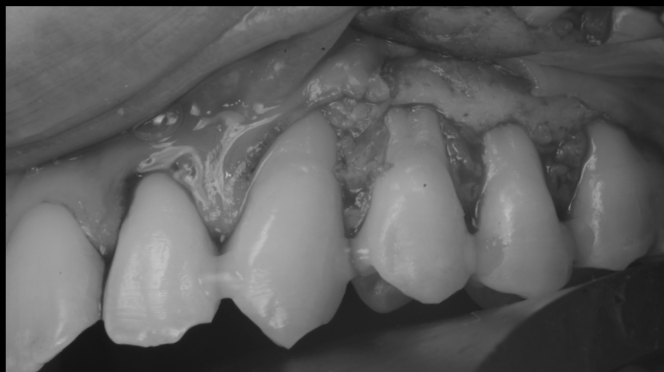

治療前

【30代男性】

歯茎の下りが気になる

【結合組織移植術】

治療で得られるメリット:歯周組織の改善、根面う蝕の予防

| 主訴 | 歯茎の下りが気になる 歯が沁みる 歯ブラシが痛い |

| 治療内容 | ルートカバー(結合組織移植術) |